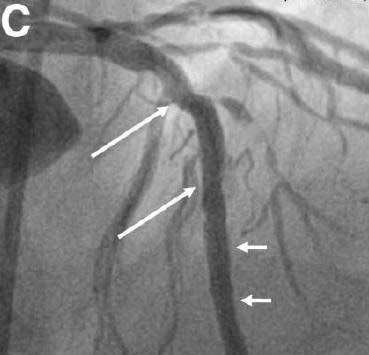

随后于该远端病变处成功置入1枚3.5×12 mm依维莫司洗脱支架(图4大箭头系原支架,小箭头系新置入支架)。随后复查OCT发现原支架近端(图5C)状态良好,无贴壁不良、支架边缘夹层或残留血栓等,并且全段内壁均有均匀的轻度内膜增生(图5D,小箭头)。两个支架之间的血管壁完好,新支架也置入良好。